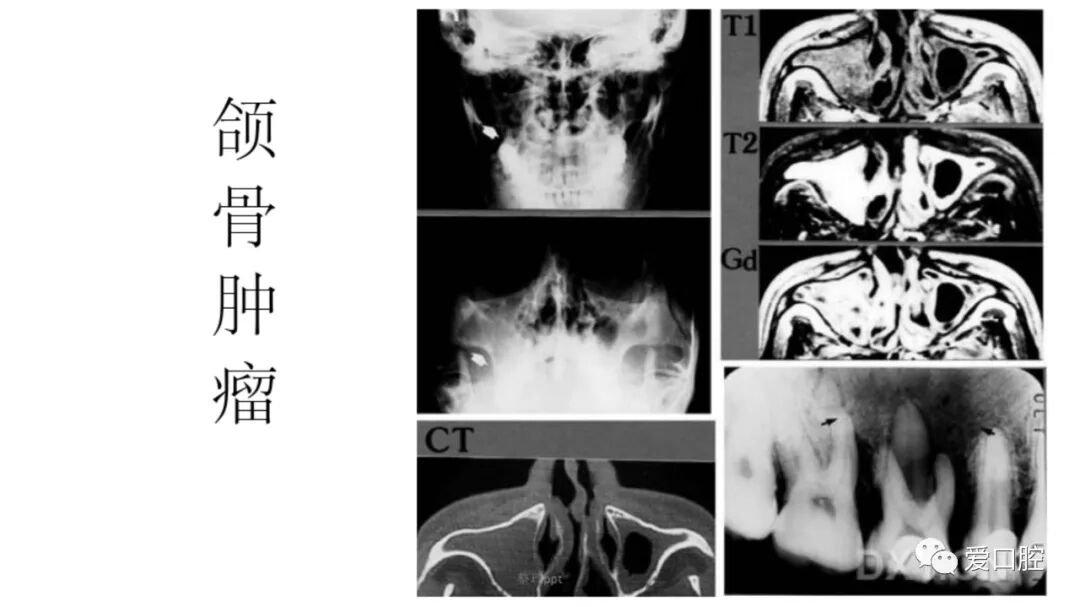

口腔小技巧 | 口腔科常见的病例影像!